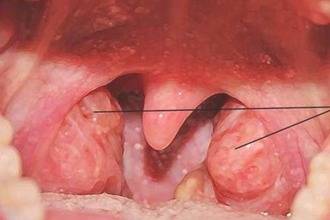

Глотка на своих поверхностях (верхней и боковых) имеет миндалины. Это скопление лимфоидной ткани носит названия: глоточная и трубные миндалины. Ниже приведена схема глотки в разрезе, которая поможет лучше представить, как она выглядит.

Небные миндалины представляют собой лимфоидную ткань и входят в состав общей иммунной системы организма, основная функция которой – это защита от инфекций. К основным симптомам тонзиллита относят:

На своде и боковых стенках носоглотки расположены миндалины, представляющие собой локальные скопления тканей лимфатической системы и участвующие в формировании местной иммунной системы. Схема носоглоточных миндалин включает в себя:

аденоиды (непарная глоточная миндалина) сверху; небные миндалины (парные) по бокам;

язычная миндалина снизу.

Таким образом, формируется своего рода защитное кольцо, препятствующее попаданию патогенов в дыхательную и пищеварительную систему.